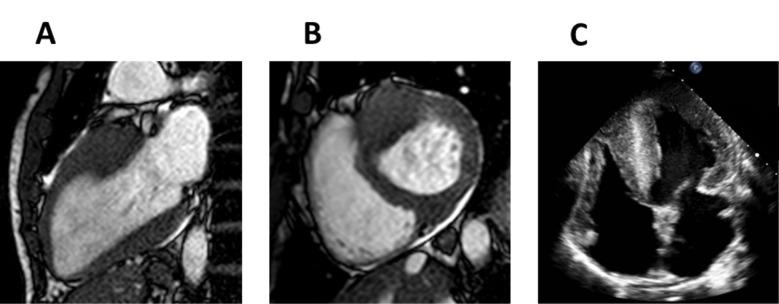

法布里病心肌病:从诊断到治疗的心脏成像作用综述

Fabry Disease Cardiomyopathy: A Review of the Role of Cardiac Imaging from Diagnosis to Treatment.

Fabry disease is a rare X-linked inherited lysosomal storage disorder caused by the absence or reduction of alfa-galactosidase A activity in lysosomes, resulting in accumulation of glycosphingolipids in various tissues. The main organ affected is the heart, which frequently manifests as left ventricular hypertrophy and can ultimately lead to cardiac fibrosis, heart failure, valve disease, cardiac conduction abnormalities and sudden cardiac death. Today we know that myocyte damage starts before these signs and symptoms are detectable on routine studies, during the designated pre-clinical phase of Fabry disease. The initiation of specific therapy for Fabry disease during the early stages of the disease has a great impact on the prognosis of these patients avoiding progression to irreversible fibrosis and preventing cardiovascular complications. Cardiac imaging has become an essential tool in the management of Fabry disease as it can help physicians suspect the disorder, diagnose patients in the early stages and improve outcomes. The recent development of novel imaging techniques makes necessary an update on the subject. This review discusses the role of multimodal imaging in the diagnosis, staging, patient selection for treatment and prognosis of Fabry disease and discusses recent advances in imaging techniques that provide new insights into the pathogenesis of the disorder and the possibility of novel treatment targets.

摘要

法布里病是一种罕见的X连锁隐性遗传性溶酶体贮积症,由溶酶体中α-半乳糖苷酶A活性缺乏或降低引起,导致糖鞘脂在各种组织中蓄积。主要受累器官是心脏,常表现为左心室肥厚,并最终可导致心脏纤维化、心力衰竭、瓣膜病、心脏传导异常和心源性猝死。如今我们知道,在法布里病的指定临床前期,即常规检查可检测到这些体征和症状之前,心肌细胞就已开始受损。在疾病早期开始对法布里病进行特异性治疗,对这些患者的预后有很大影响,可避免进展为不可逆纤维化并预防心血管并发症。心脏成像已成为法布里病管理中的一项重要工具,因为它有助于医生怀疑该病、在早期诊断患者并改善预后。新型成像技术的最新发展使得有必要对该主题进行更新。本综述讨论了多模态成像在法布里病的诊断、分期、治疗患者选择和预后中的作用,并讨论了成像技术的最新进展,这些进展为该疾病的发病机制和新治疗靶点的可能性提供了新见解。